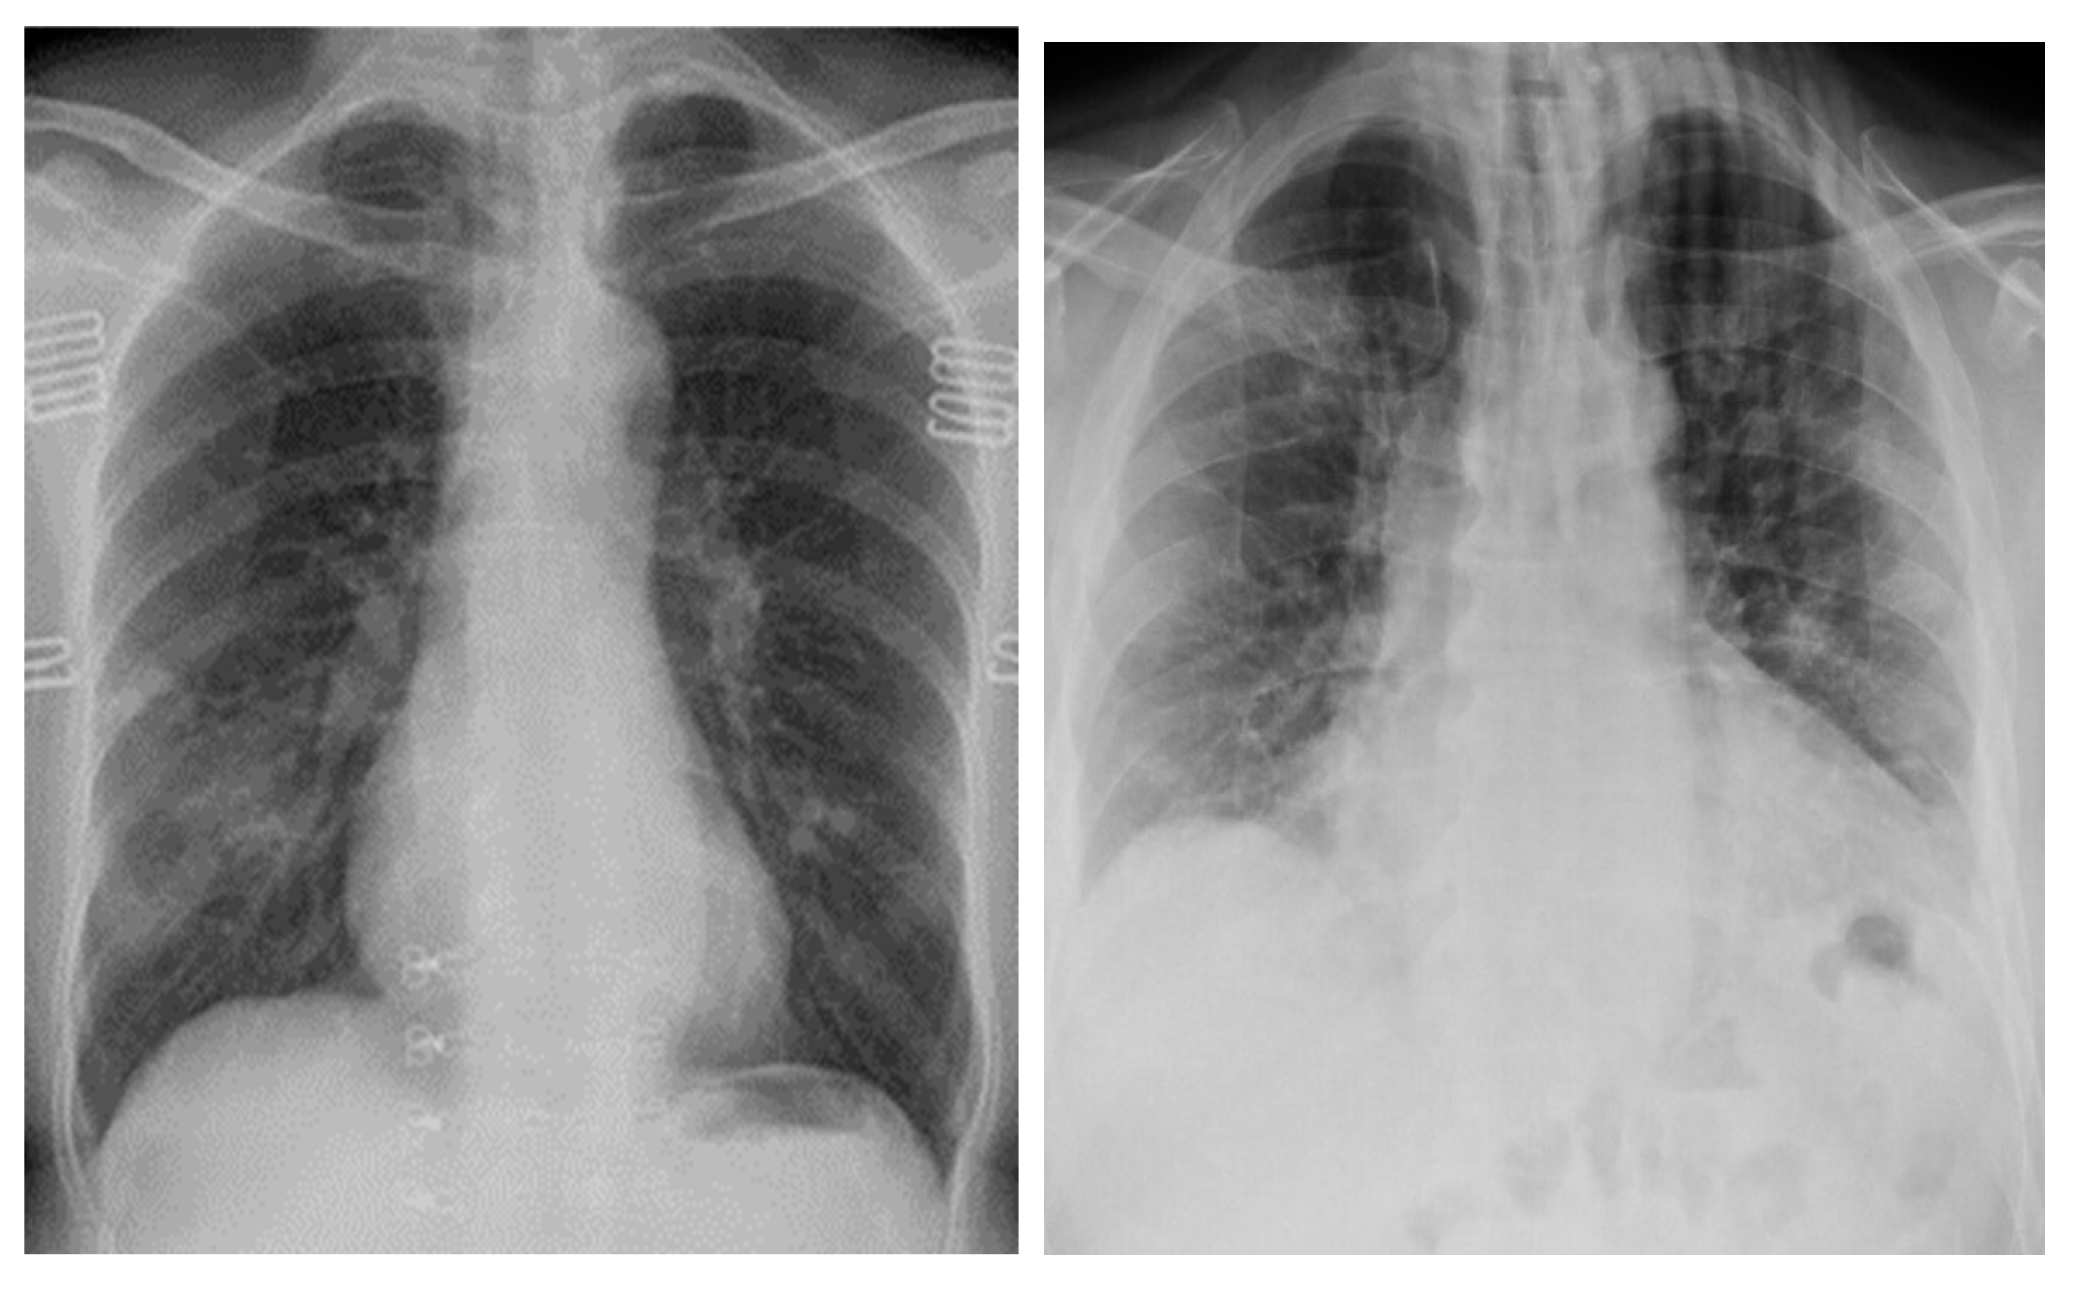

The COVID-19 positive images used to train the GAN models came from the COVID-19-radiography database from Kaggle, [10,11]. The repository consists of 3616 COVID-19 positive images, 10,192 normal lung images, 6012 non-COVID lung infection images, and 1345 viral pneumonia images. All images were resized to 299 × 299. In this paper, we will only be using the COVID-19 positive chest X-ray images to train the GAN model, as our objective is to generate COVID-19 chest X-ray images. Examples of COVID-19 positive chest X-ray images is shown in Figure 1 below.

Figure 1.

COVID-19 Positive X-ray Images.